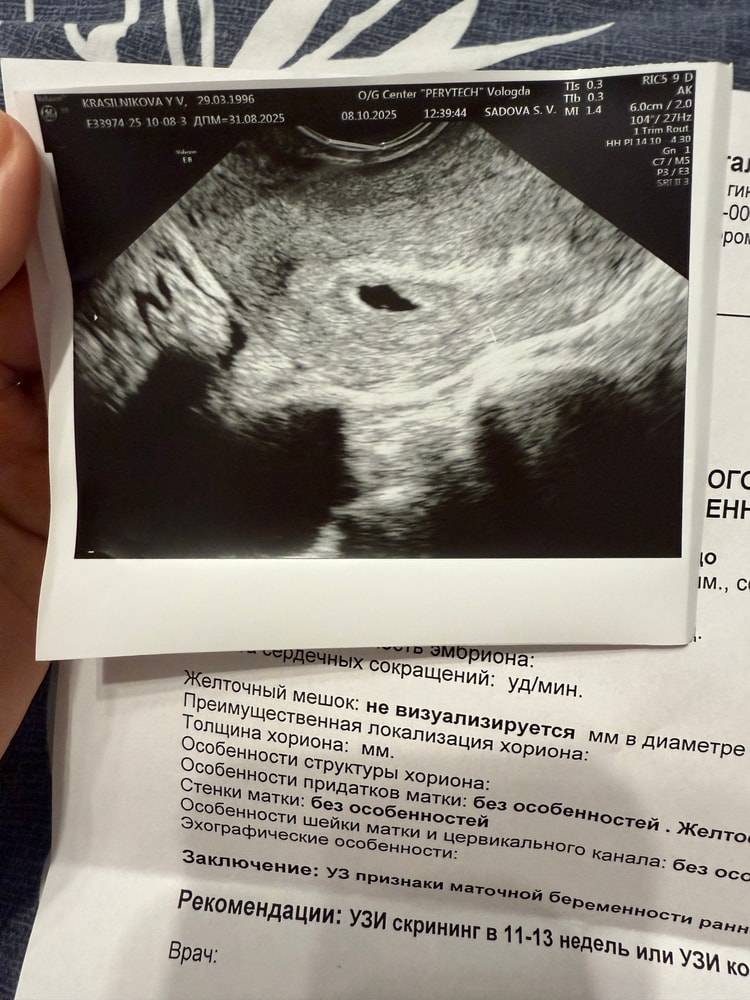

Здравствуйте. Дата последних месячных 31 августа 2025 г, сегодня была на узи, размер плодного яйца 6,7 мм, желточный мешок не визуализируется. Эмбриона тоже не видно. Желтое тело СвД 16 мм. Рекомендовано узи через 14 дней. Скажите, пожалуйста, стоит ли уже обеспокоиться? Тип узи сканера ge voluson e8 BT16 3 беременность, 1 удачная, 2 замершая